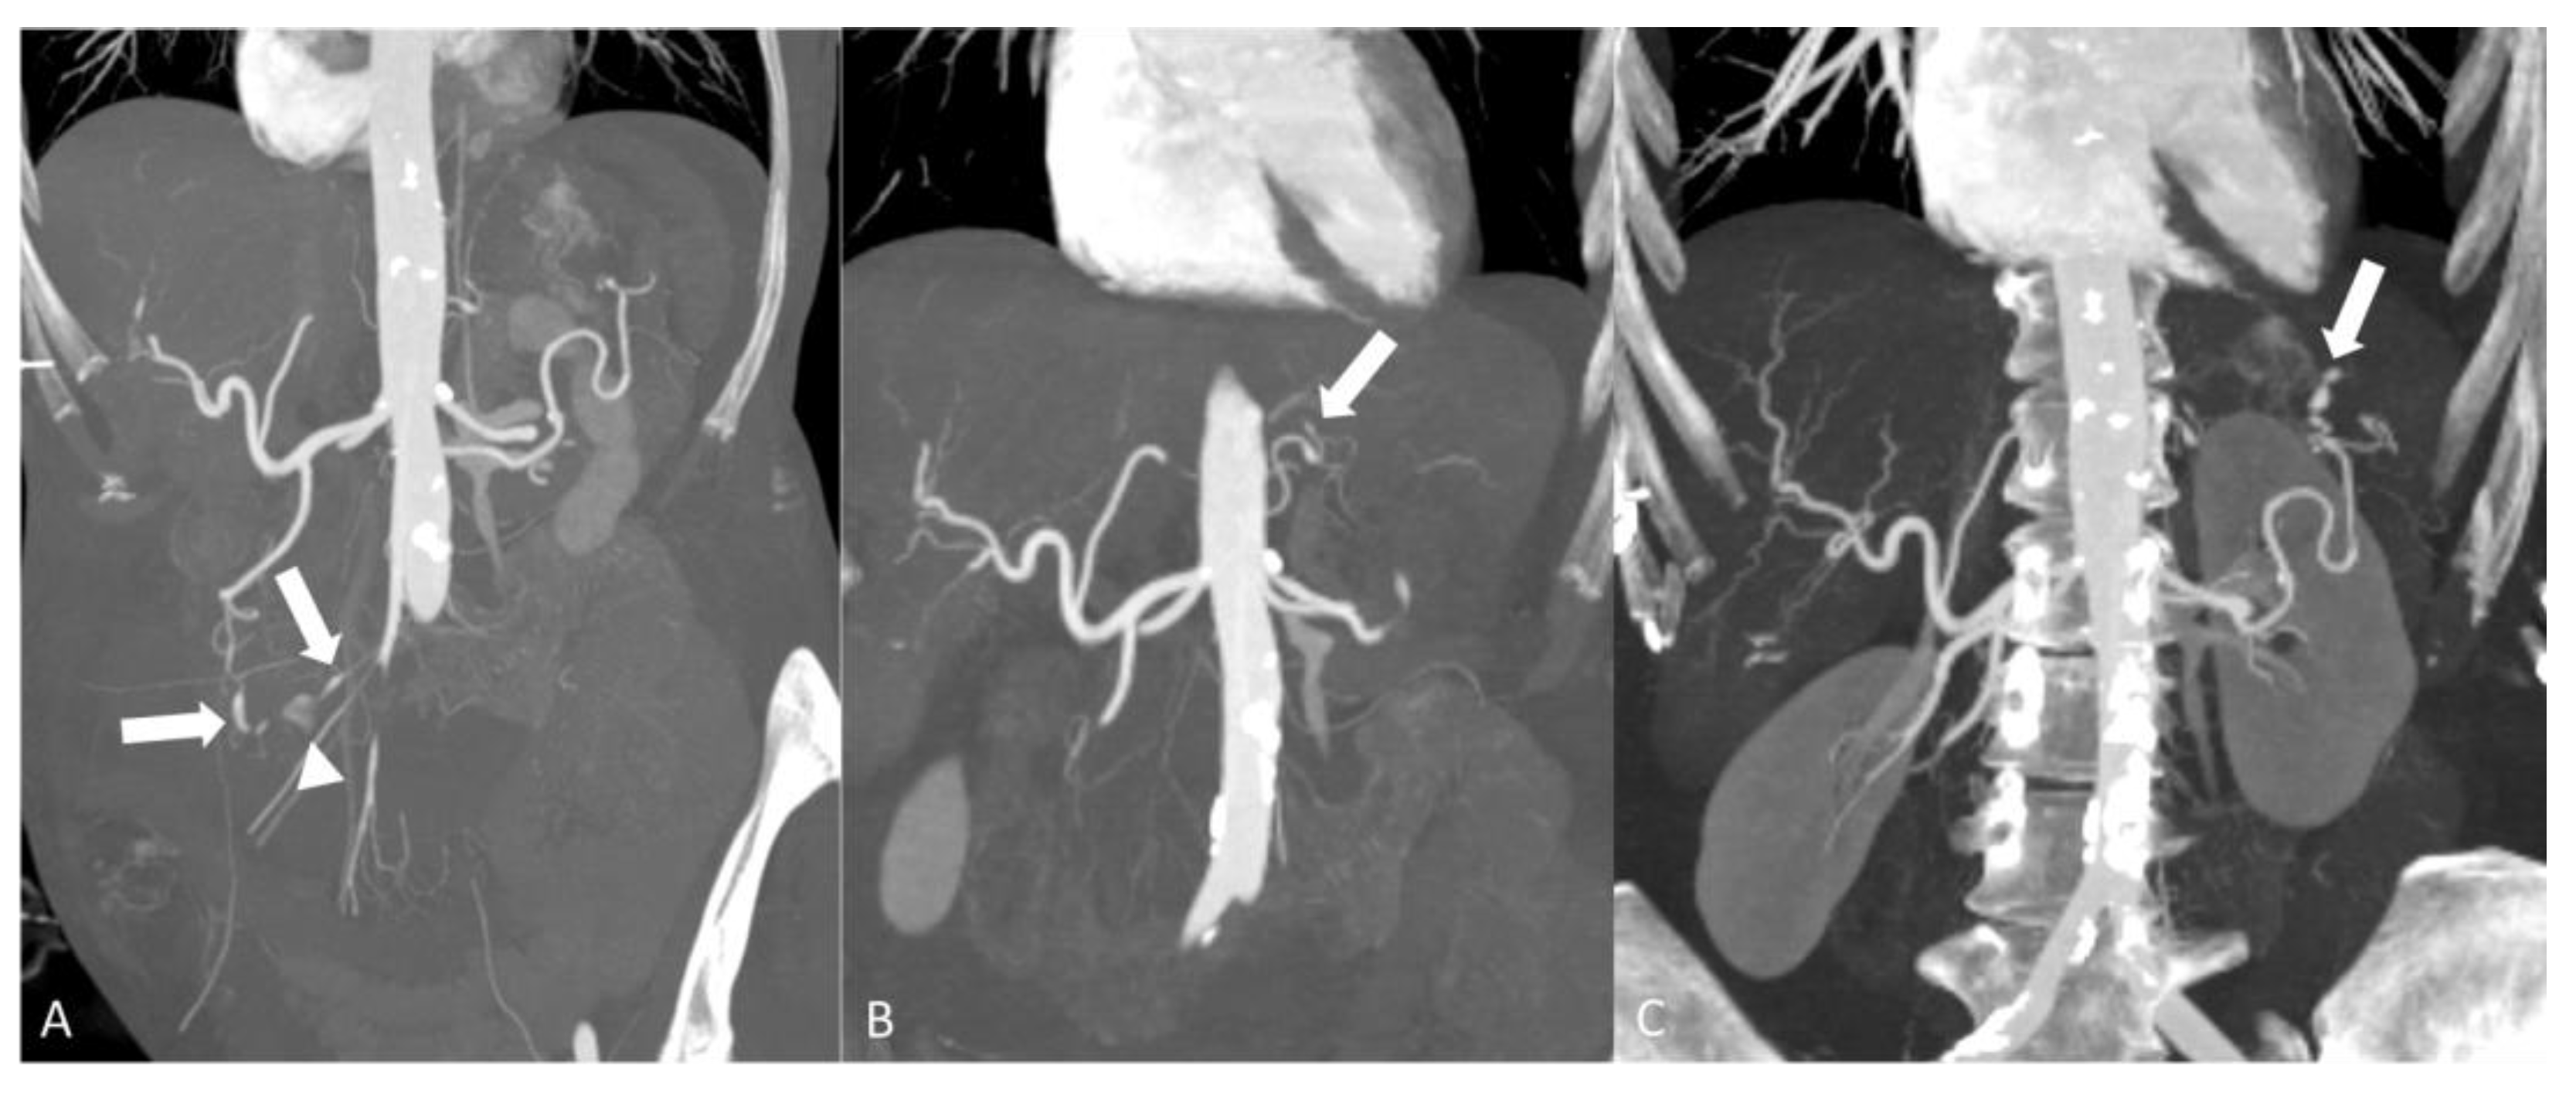

2.2.1. Polyarteritis Nodosa

- Singhal, M.; Gupta, P.; Sharma, A.; Lal, A.; Rathi, M.; Khandelwal, N. Role of multidetector abdominal CT in the evaluation of abnormalities in polyarteritis nodosa. Clin. Radiol. 2016, 71, 222–227. [Google Scholar] [CrossRef] [PubMed]

- Chen, Z.; Zhao, Y.; Wang, Q.; Li, Y.; Li, H.; Zhou, Y. Imaging features of 18F-FDG PET/CT in different types of systemic vasculitis. Clin. Rheumatol. 2022, 41, 1499–1509. [Google Scholar] [CrossRef] [PubMed]

- Chung, S.A.; Gorelik, M.; Langford, C.A.; Maz, M.; Abril, A.; Guyatt, G.; Archer, A.M.; Conn, D.L.; Full, K.A.; Grayson, P.C.; et al. 2021 American College of Rheumatology/Vasculitis Foundation Guideline for the Management of Polyarteritis Nodosa. Arthritis Rheumatol. 2021, 73, 1384–1393. [Google Scholar] [CrossRef] [PubMed]